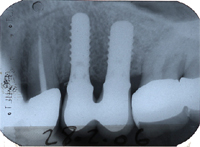

Bei einer 59 Jahre alten Frau muss wegen Wurzelbruchs und Vereiterung des ersten Brückenpfeilers (1. Zahn im Röntgenbild von Abb. 1 links) ein Zahn gezogen und das folgende Zwischenglied der Brücke rechts davon (schwarze Pfeile in Abb. 1) entfernt werden. Es entsteht im Oberkiefer links eine unschöne, ästhetisch sehr empfindliche Lücke von 14 mm.

In Abb. 2 sieht man, wie wir einen Sinuslift gemacht haben, um zwei Implantate setzen zu können. Dabei verwendeten wir ein Transplantationsgemisch mit 10% Eigenknochen und 90% Substitut. Der ortsständige Knochen beträgt beim ersten Implantat 12 mm (nur die Implantatspitze hätte in den ehemaligen Sinus geragt), beim zweiten Implantat 6 mm.

In Abb. 3 sind die zementierten Implantatkronen sieben Monate nach dem Sinuslift im Röntgenbild zu sehen. Die eigenen, bestehenden Kronen hinter den neuen Implantatkronen konnten somit gerettet werden. Abb. 4 zeigt das klinische, intraorale Resultat zwei Jahre nach der Behandlung und Abb. 5 das "happy smiling" der extraoralen Situation nach der Behandlung.